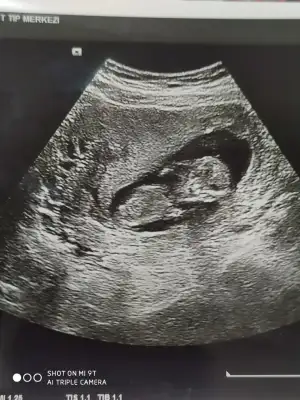

Erkek12 haftalık bana da bakabilir misiniz![]()

Diğer taraftaki konumda yazdim erkek gibi sanki tekrar USG paylasin12 haftalık bana da bakabilir misiniz![]()

12 haftalık USG bu çok teşekkür ederimDiğer taraftaki konumda yazdim erkek gibi sanki tekrar USG paylasin

Başka USG paylaşın12 haftalık USG bu çok teşekkür ederim![]()